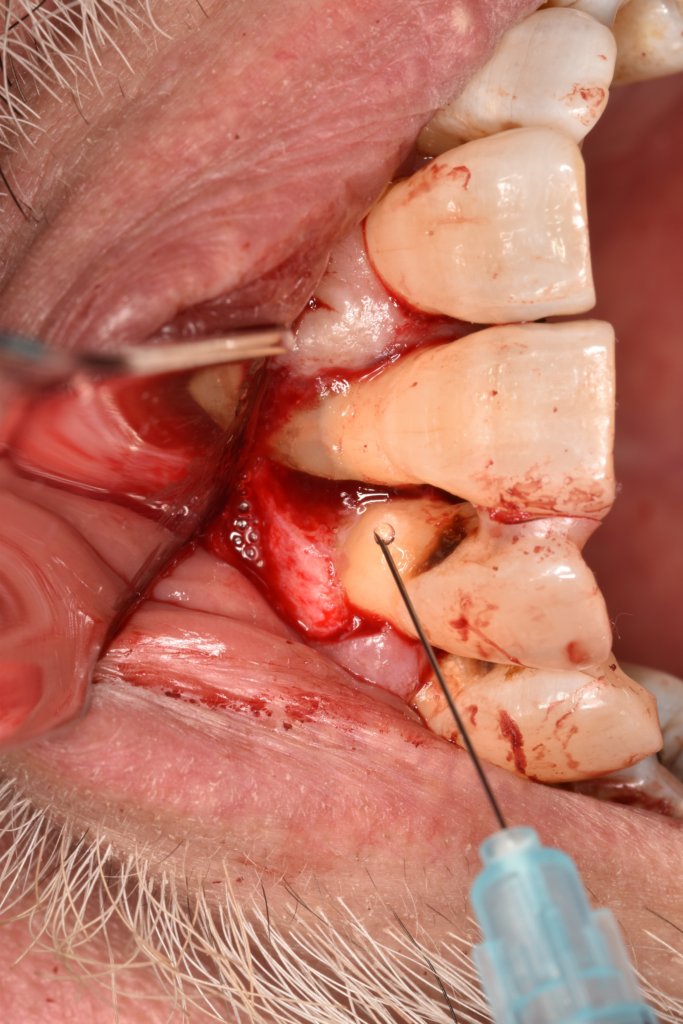

↑レントゲンで骨吸収を認めます。歯肉を切開すると実際に骨がありません。